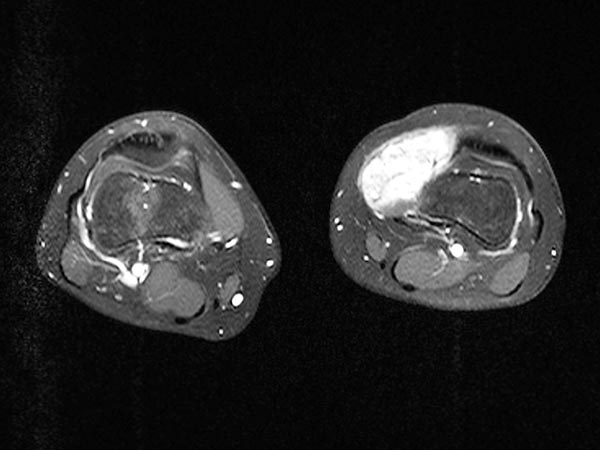

Die vollständig verschlossene venöse Malformation, die atypischerweise deutliche arteriovenöse Fisteln enthielt, konnte nach erfolgreicher Embolisation und Sklerosierungsbehandlung mit vollständigem Verschluss erfolgreich offen reseziert werden. Die axiale T2-gewichtete MRT zeigt die Vollständigkeit der Resektion ohne eine verbliebene Läsion.

Die vollständig verschlossene venöse Malformation, die atypischerweise deutliche arteriovenöse Fisteln enthielt, konnte nach erfolgreicher Embolisation und Sklerosierungsbehandlung nach vollständigem Verschluss erfolgreich offen reseziert werden. Die Patientin ist seither asymptomatisch (3 Jahre, 4 Monate).